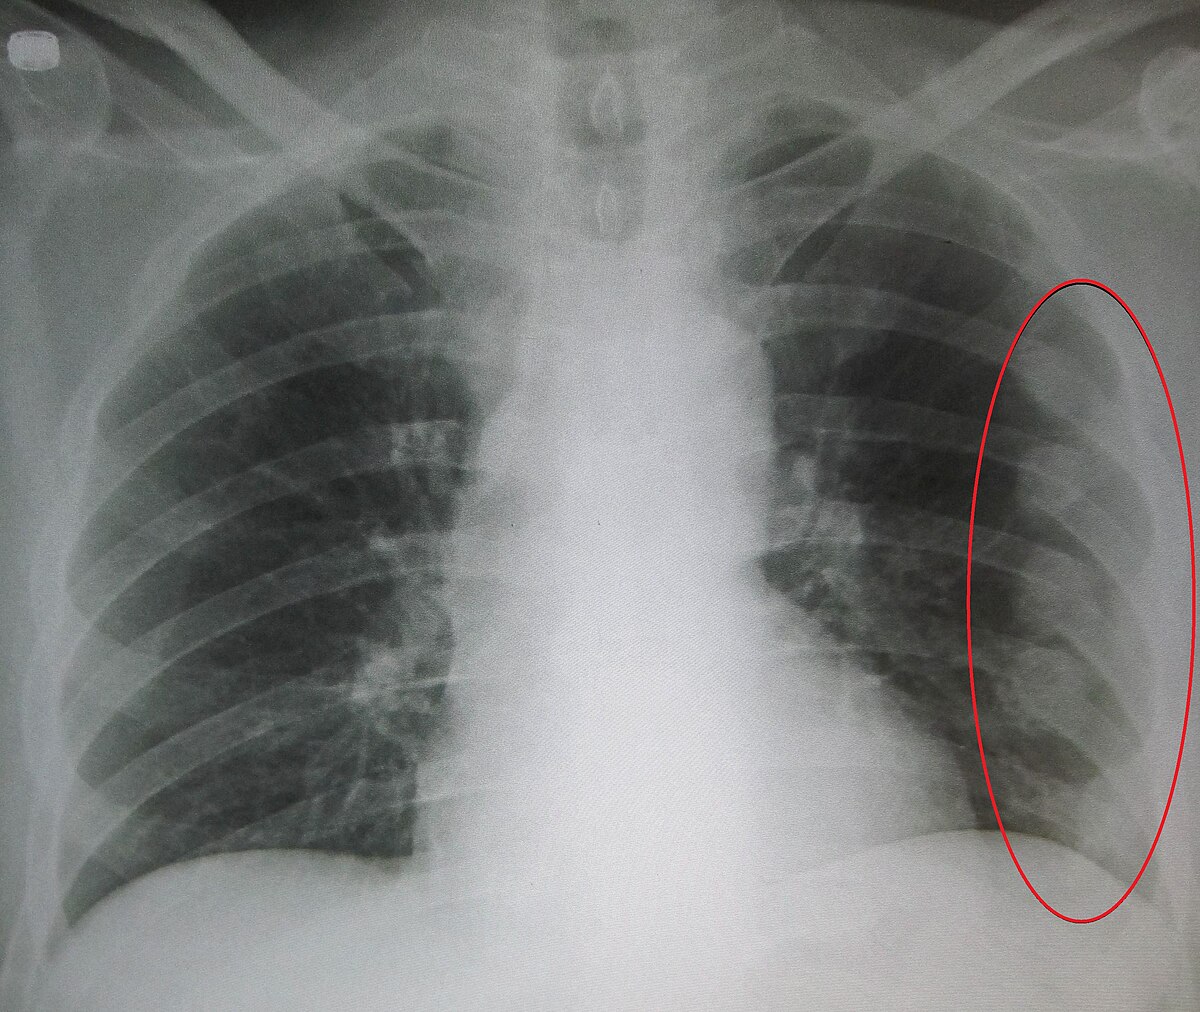

갈비뼈 금이갔을때빨리낫는법(rib fracture treatment), 골절에 좋은 음식

갈비뼈가 금이 간다면, 그 부위가 특별히 예민하고 치료하기가 어려운 부위입니다. 일반적으로 팔이나 다리와 같은 부위의 골절과는 달리 깁스를 사용하기가 어렵기 때문에 치료에는 몇 가지 주의가 필요합니다. 여기서는 갈비뼈가 금이 갔을 때의 증상과 갈비뼈 금이 갔을 때 빨리 낫는 법에 대해 알아보겠습니다.